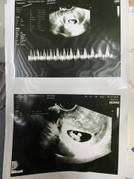

มีใครซาวด์ตอนอายุครรภ์8 สัปดาห์แล้วเจอตัวทารกในครรภ์บ้างคะ

ทางนี้คุณหมอนัดซาวด์อีก3สัปดาห์ค่ะ อยากเห็นรูปใบซาวด์ของแม่ๆแต่ละคน ว่าเห็นตัวน้องมั้ยค่ะ☺️👶🏻📝 #ขอบคุณสำหรับคำตอบค่ะ #ขอคำแนะคำปรึกษาคะ

บ้านนี้ฝากครรภ์ตอน 8+3 วีค เจอน้องแล้วได้ยินเสียงหัวใจด้วยค่ะ

บ้านนี้ก็ซาวด์ตอน 8 สัปดาห์ค่ะ เจอนะคะ

บ้านนี้ซาวตอน 8 สัปดาห์เจอน้องแล้วค่ะ

ซาวด์ผ่านช่องคลอดตอน8วีคพอดีเป๊ะค่ะ